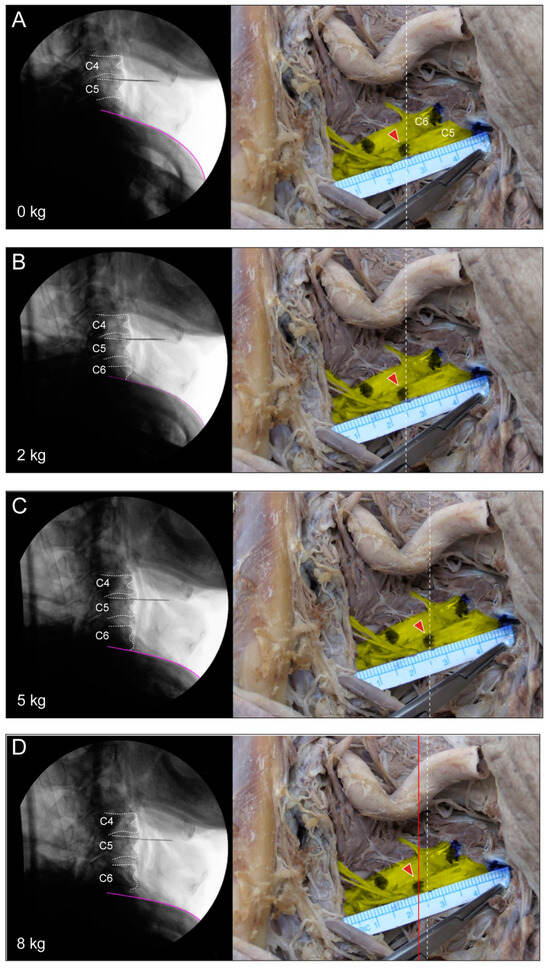

In the third experiment, after further dissection, the mean length of C5 increased from 0.75 mm to 5.31 mm at 5 kg, and that of C6 increased from 0.5 mm to 5.44 mm at 5 kg. The initial extended length measured at 5 kg was slightly shorter for C6, but it was observed that the increase was greater than that for C5 as force was applied (Figure 4, Table 2).

Figure 4.

(A–G) Fluoroscopic lateral view and unadulterated findings of a stretched root at each traction force. Indication of lateral view located in the C4–5 intervertebral space and the inferior purple line indicates the upper margin of the clavicle. Each traction force is 0, 2, 5, 12, 15, and 20 kg. As the traction force increases, the visible range of the lower cervical vertebrae increases in the lateral image, and, finally, the inferior margin of the C7 endplate is visible at a force of 20 kg. The vertical dotted line (white) on the right unadulterated photo shows a point 2.5 cm away from the extraforaminal origin. How much the root stretches as more traction force is applied can be seen by the red arrow with a vertical line (red) and the point marked on the nerve root moving away from the dotted line.

An analysis of the elongation lengths of cervical fifth and sixth nerve roots using a nonparametric test (Kruskal–Wallis test) revealed a significant increase in the average value as the traction force increased (Table 2).